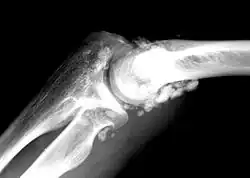

| X-ray of an elbow affected by synovial chondromatosis | |

Synovial chondromatosis is a locally aggressive bone tumor of the cartilaginous type.[1] It consists of several hyaline cartilaginous nodules and has the potential of becoming cancerous.[1]

Rare and little known, with currently no known cure, the disease gradually forms blisters in the thin flexible membrane of the synovium, which calcify and enlarge. These nodules eventually break free and float around the joint space becoming larger – these add to the discomfort and stiffness of the joint. The affected tissue will show up as a semi-solid mass in an MRI scan, final diagnosis is usually confirmed by taking a biopsy. The disease generally affects only one of the larger weight bearing joints (hip, ankle, knee) – although the elbow, and wrist can also be affected. It rarely involves the temporomandibular joint (TMJ) and most publications are case reports.[3]